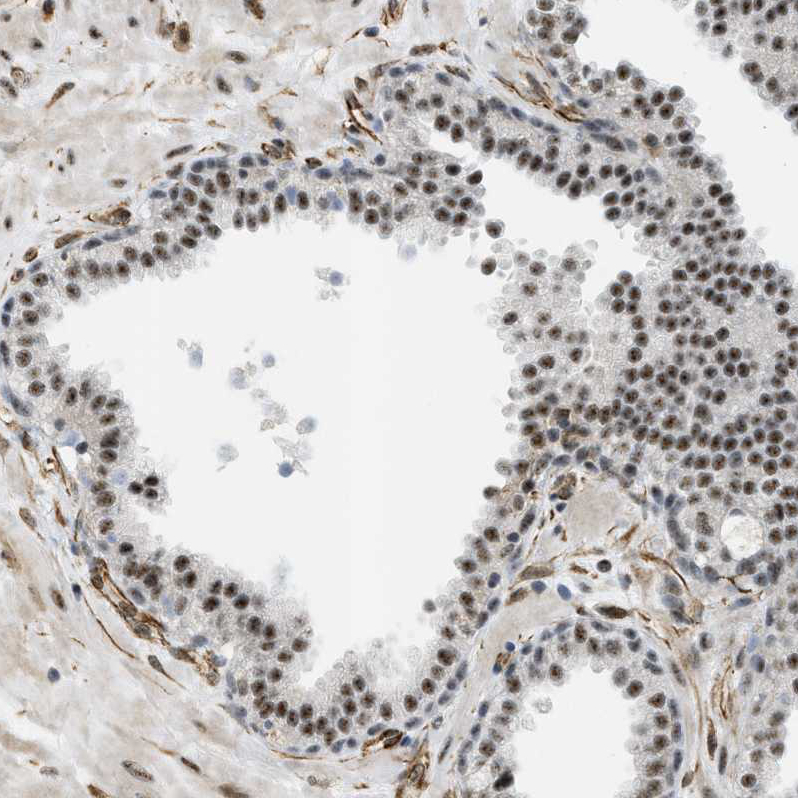

Immunohistochemical staining of human cerebral cortex shows strong nuclear positivity in neurons.